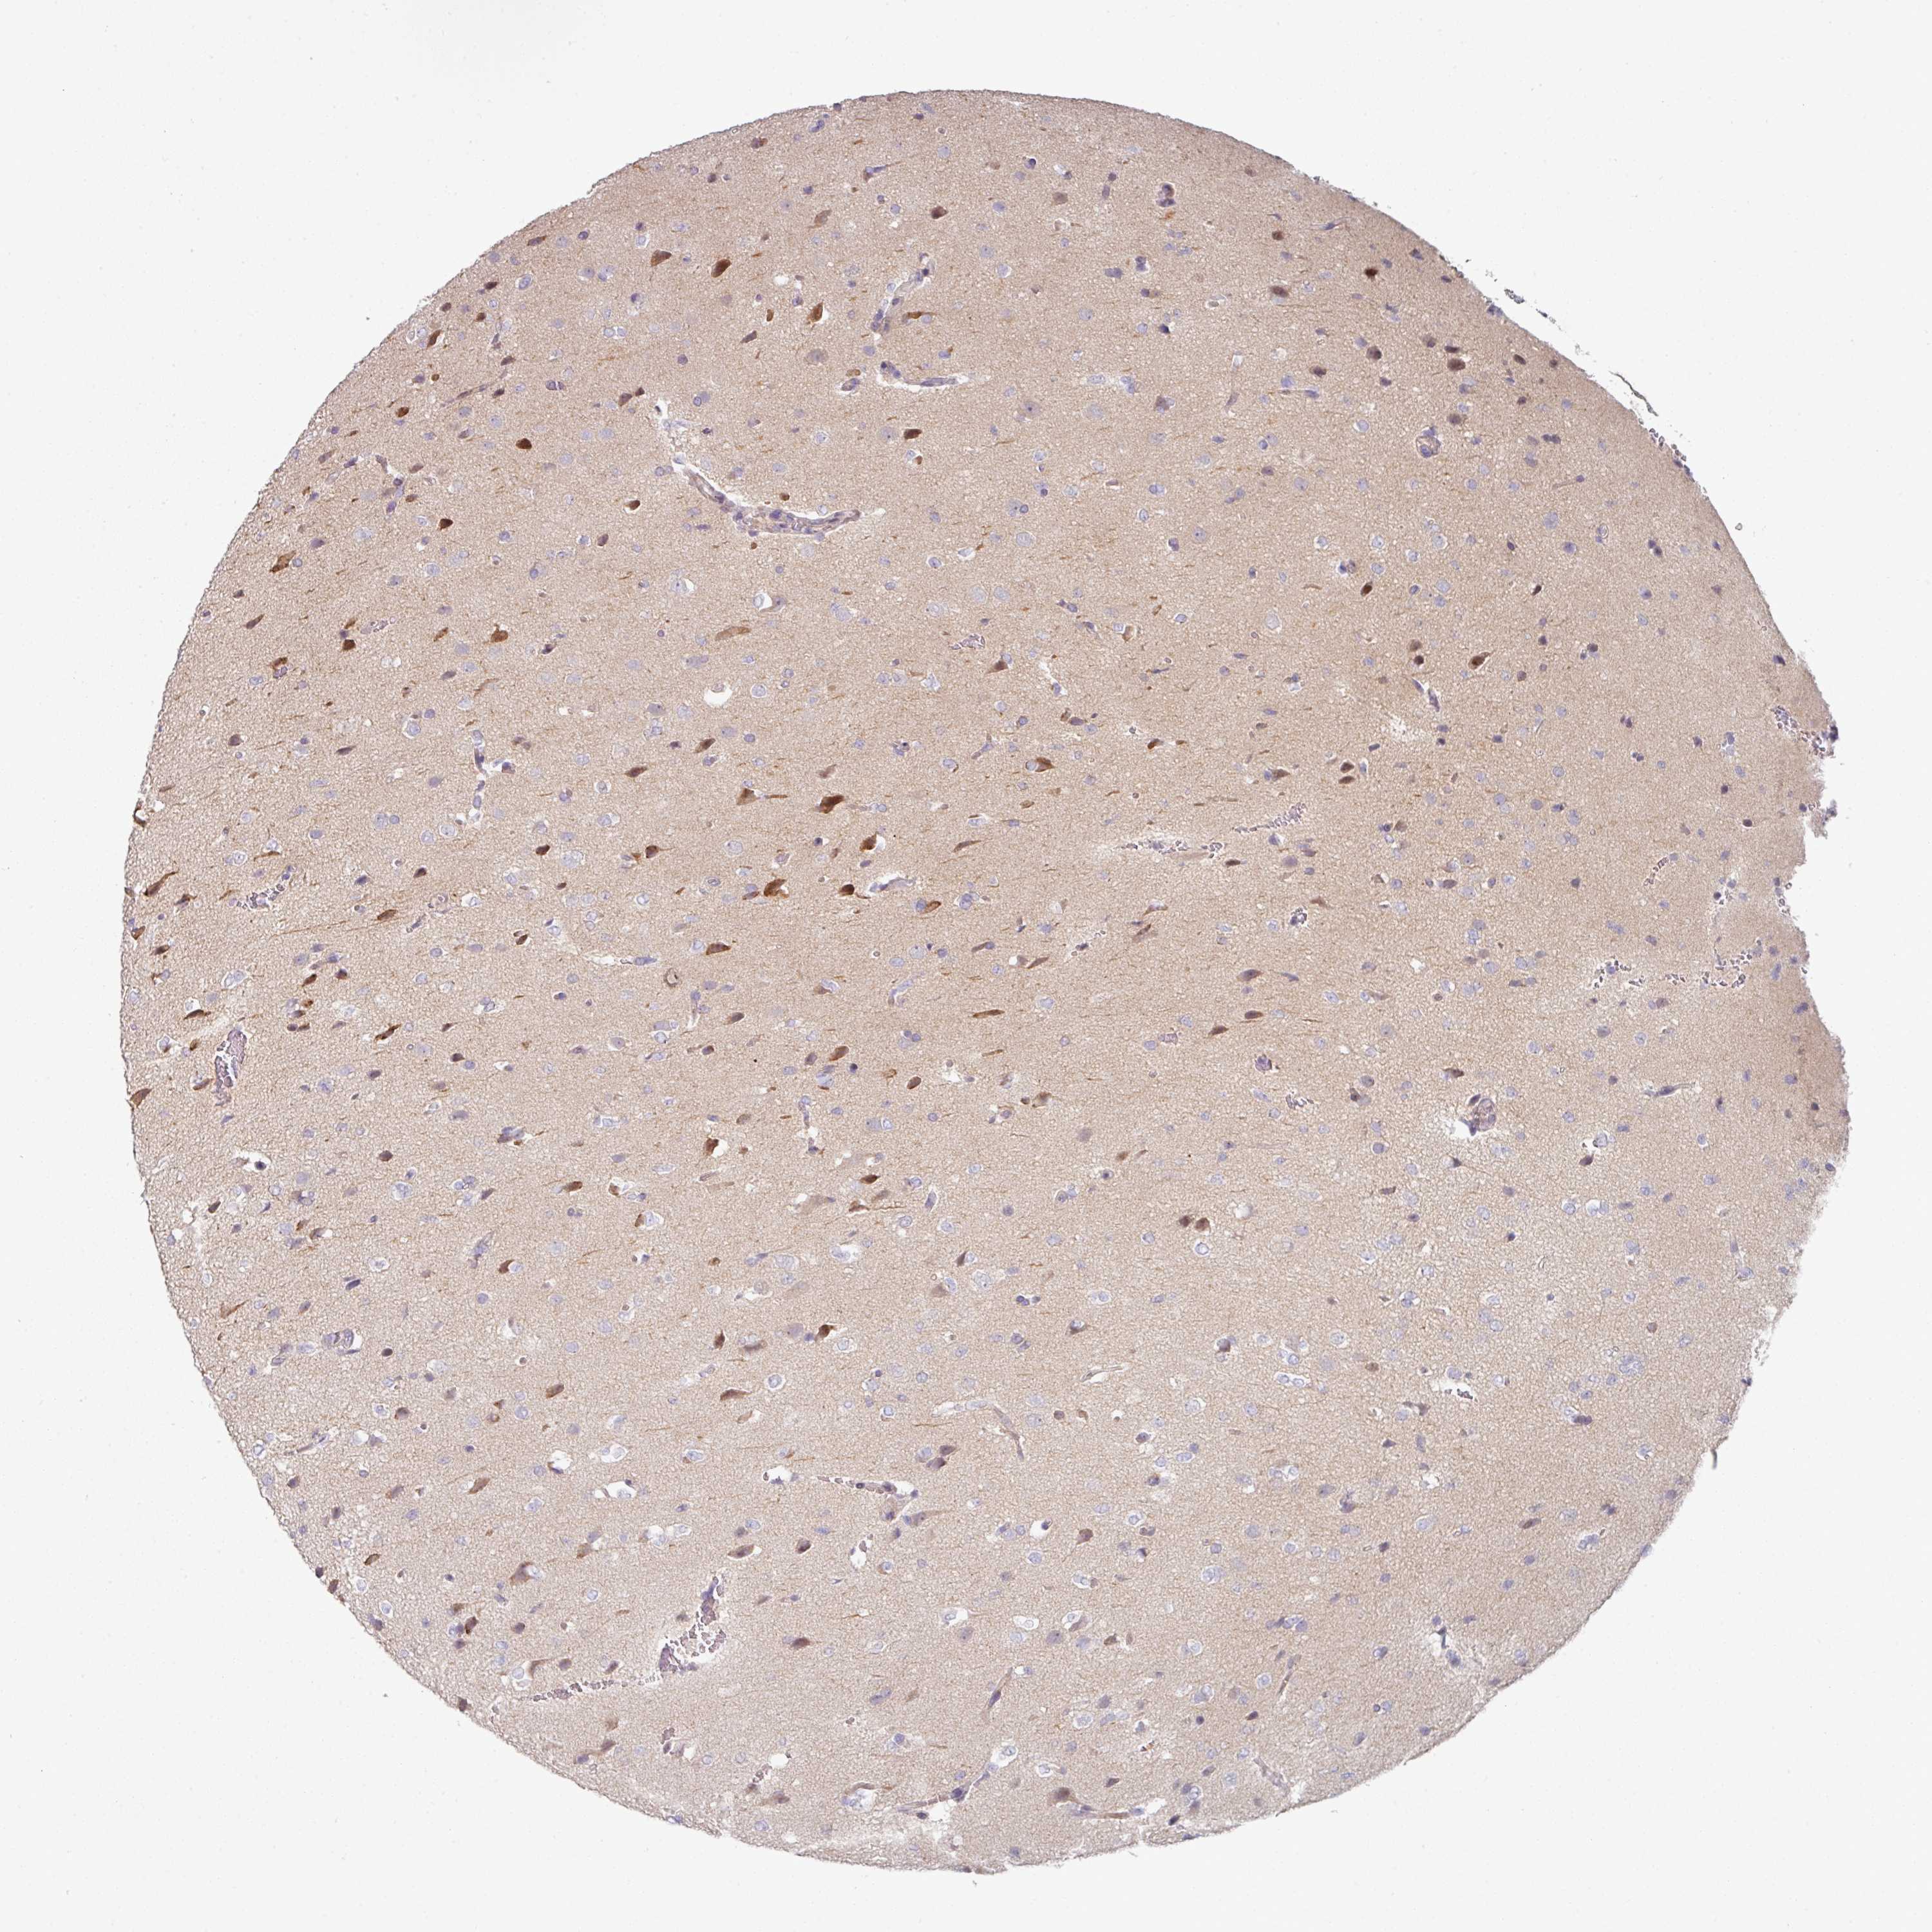

GLIOMA - Protein expressioni

A mouse-over function shows sample information and annotation data. Click on an image to view it in a full screen mode. Samples can be filtered based on level of antibody staining by selecting one or several of the following categories: high, medium, low and not detected. The assay and annotation is described here.

Note that samples used for immunohistochemistry by the Human Protein Atlas do not correspond to samples in the TCGA dataset.

Antibody stainingi

Antibody staining in the annotated cell types in the current human tissue is reported as not detected, low, medium, or high, based on conventional immunohistochemistry profiling in selected tissues. This score is based on the combination of the staining intensity and fraction of stained cells.

Each image is clickable and will lead to virtual microscopy that enables deeper exploration of all samples and also displays staining intensity scores, fraction scores and subcellular localization as well as patient and tissue information for each sample.

Antibody HPA052606

Antibody HPA077139

Glioma, malignant, Low grade

Glioma, malignant, High grade

Glioma, malignant, NOS